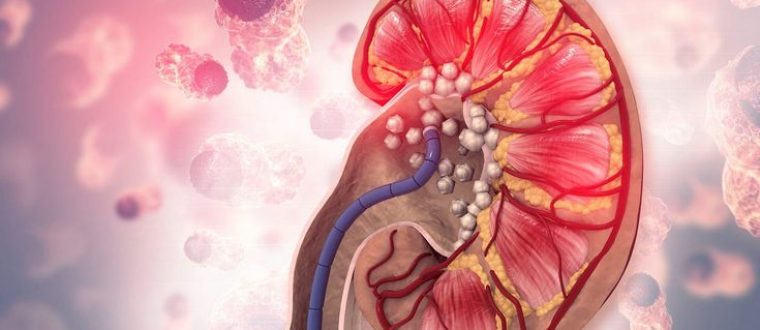

אבני הכליות הנפוצות ביותר הן אוקסלאט הסידן ופוספאט הסידן. אחריהן באות אבנים הנוצרות מחומצת שתן. אבנים בכליות הן תופעה נפוצה

אבני הכליות הנפוצות ביותר הן אוקסלאט הסידן ופוספאט הסידן. אחריהן באות אבנים הנוצרות מחומצת שתן. אבנים בכליות הן תופעה נפוצה

כל כליה מכילה כמיליון נפרונים, שמספרם הולך ויורד במשך החיים. ירידה הדרגתית בתפקוד הכליות אינה מורגשת עד שנהרסים כ- 70%